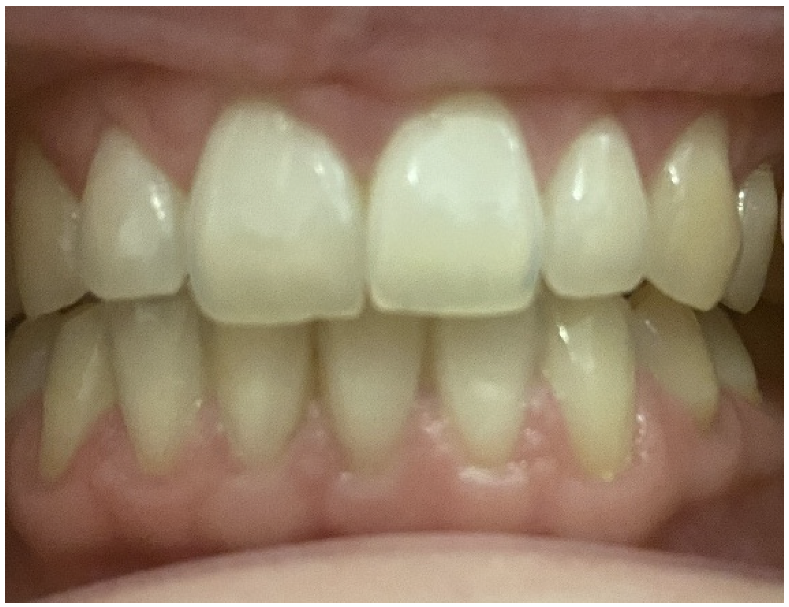

2.3. Oral Examination